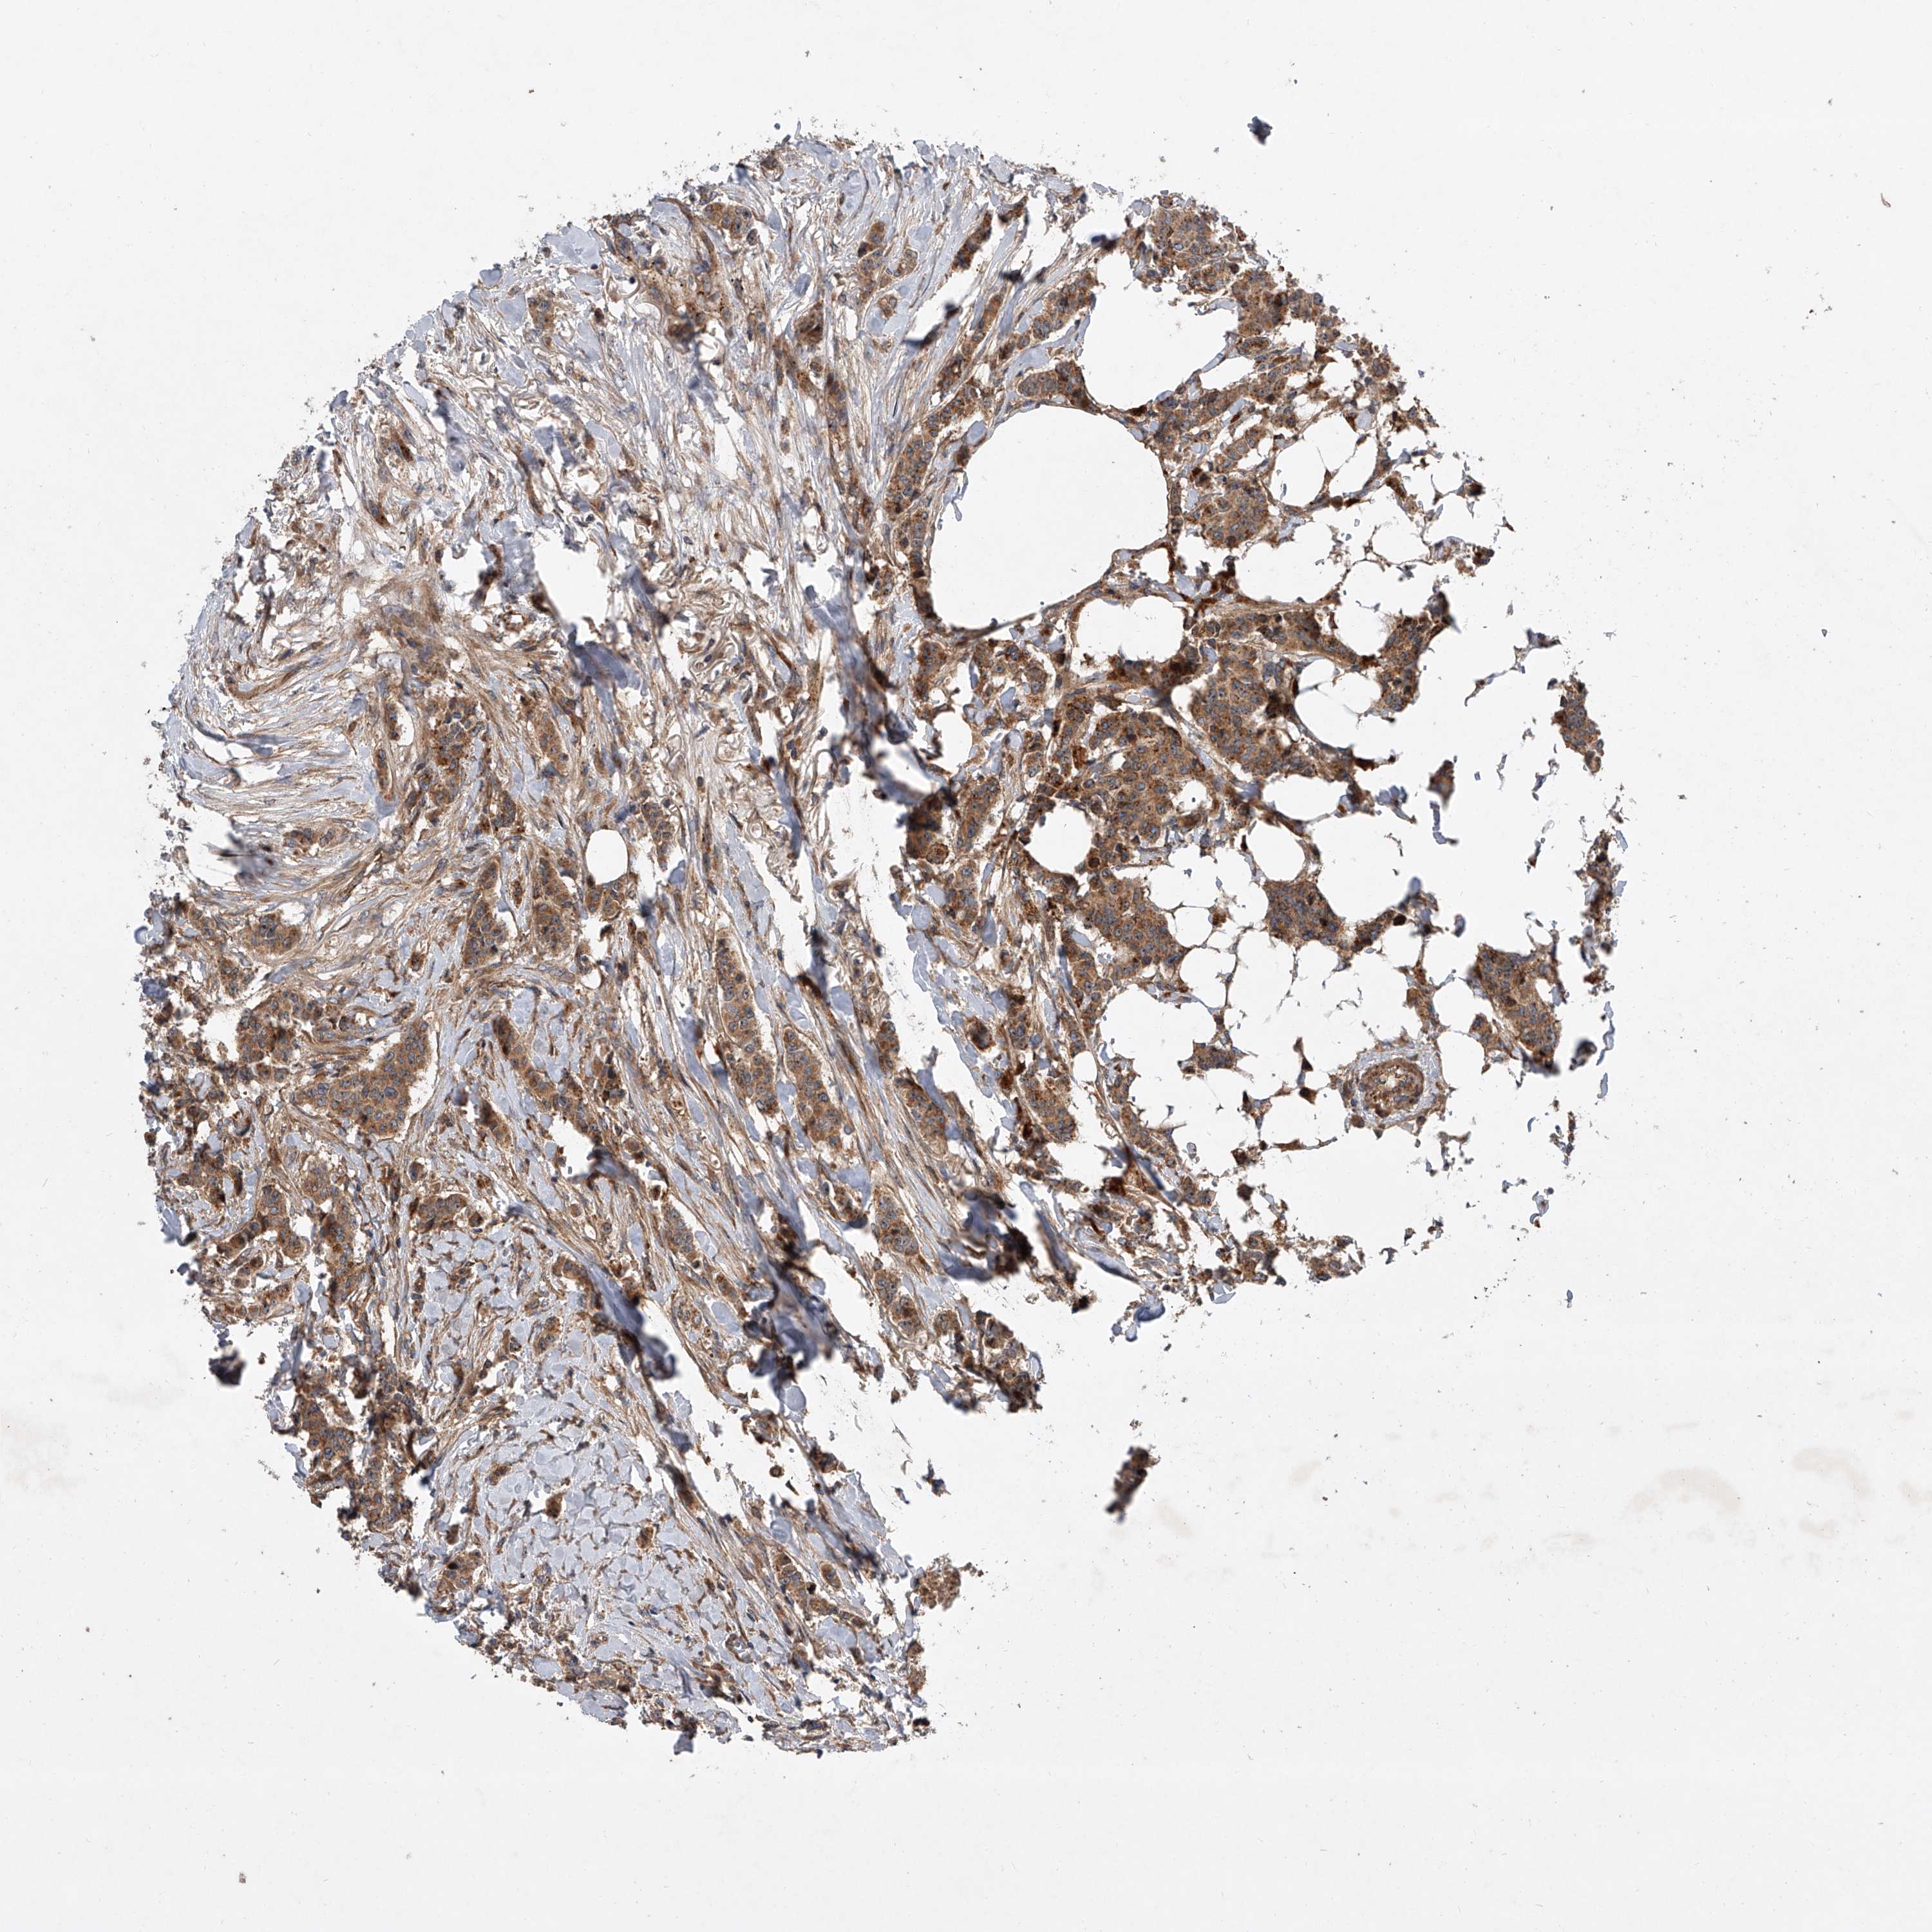

CANCER BREAST CANCER Show tissue menu

BRCA TCGA BRCA VALIDATION PROTEIN EXPRESSION